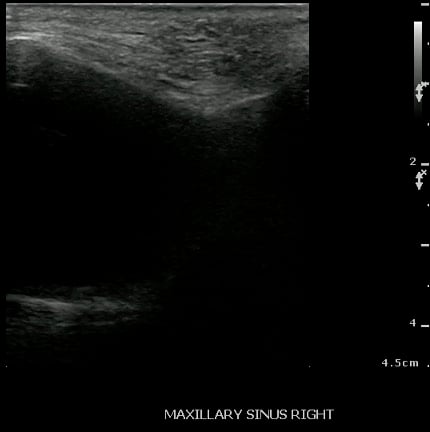

- Normal Maxillary Sinus:

- The normally air-filled maxillary sinus prevents the transmission of ultrasound beams (Air reflects most of the signal, thus preventing visualization of deep structures).

- The anterior maxillary sinus wall produces a bright echo in the near field, with reverberation artifact posteriorly (producing a snowstorm appearance), and preventing visualization of the posterior wall.

- Figure 27 and 28. Normal maxillary sinus

- Sinus fluid (Maxillary Sinusitis):

- Figure 29 and 30. Sinusitis

- If the sinus cavity is fluid-filled, then the ultrasound signal will penetrate through the thin hyperechoic anterior wall, through the anechoic appearing fluid in the sinus cavity, and reflect off of the posterior walls, thus producing an image of the entire sinus cavity (Sinusogram) with the posterior wall of the sinus seen as a bright echogenic line in the far-field of the image.